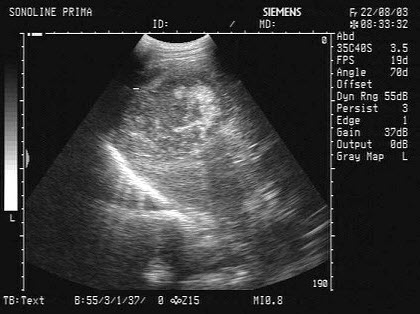

患者女47岁,皮肤、巩膜黄染,进行性加重2个月余,腹痛、腹胀,既往有胆结石病史。B超检查如图所示,根据超声声像图,诊断为()

某患者左腹部疼痛,根据左肾区超声声像图,最可能的诊断为()

A.左肾结石并左肾积水

B.左输尿管结石并左肾重度积水

C.左输尿管结石

D.左肾结石

E.左输尿管结石并左肾轻度积水